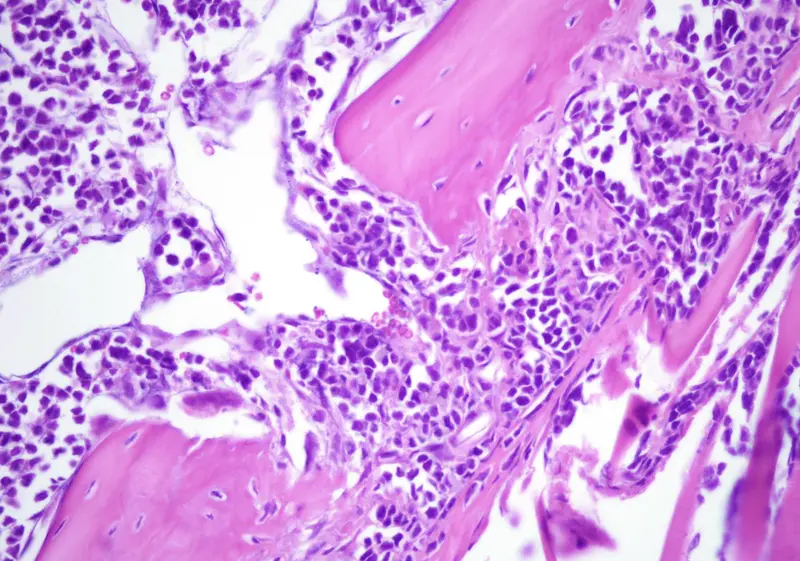

Archivo - Lesión Litica del modelo de Mieloma Múltiple/ CSIC - CSIC - Archivo

El mieloma múltiple es el tercer tumor hematológico en frecuencia, ya que representa el 1 por ciento de todas las neoplasias y el 10 por ciento de las neoplasias hematológicas. Se trata de un cáncer de las células plasmáticas, situadas en la médula ósea, cuyo rol es crucial en el sistema inmunitario.